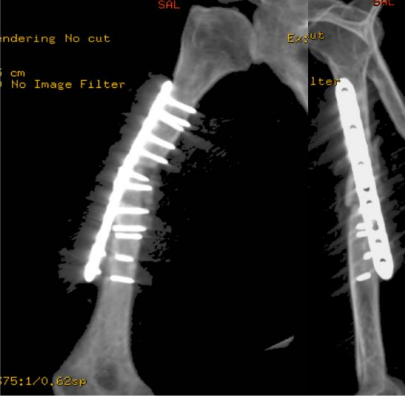

We present a case of recalcitrant humeral shaft nonunion in a 55-year-old obese female with type II diabetes, hypertension, and dyslipidemia. She sustained a rt humeral fracture in September 2017 and was treated at other facility with regular with 3.5 LC-DCP using 2 lag, 2 cortical, 6 locking , and 23 June 2018, she presented to the emergency after hearing a sudden pop associated with severe pain while performing daily activity with no significant trauma. Clinical examination revealed a healed surgical scar on the lateral aspect of the right arm, tenderness on palpation over the mid portion of the right arm, limitation of movement of the right shoulder and elbow due to pain, and intact distal pulses with no neurological deficits. Imaging in the form of X-rays revealed non-united right humeral shaft fracture. The fracture edges were smooth and partly sclerotic, with failure of a 3.5 mm locking compression plate was present in the form of plate fracture and screw pull-out at the level of the fracture (Figure 1). Laboratory investigations were negative for infection.

Figure 01